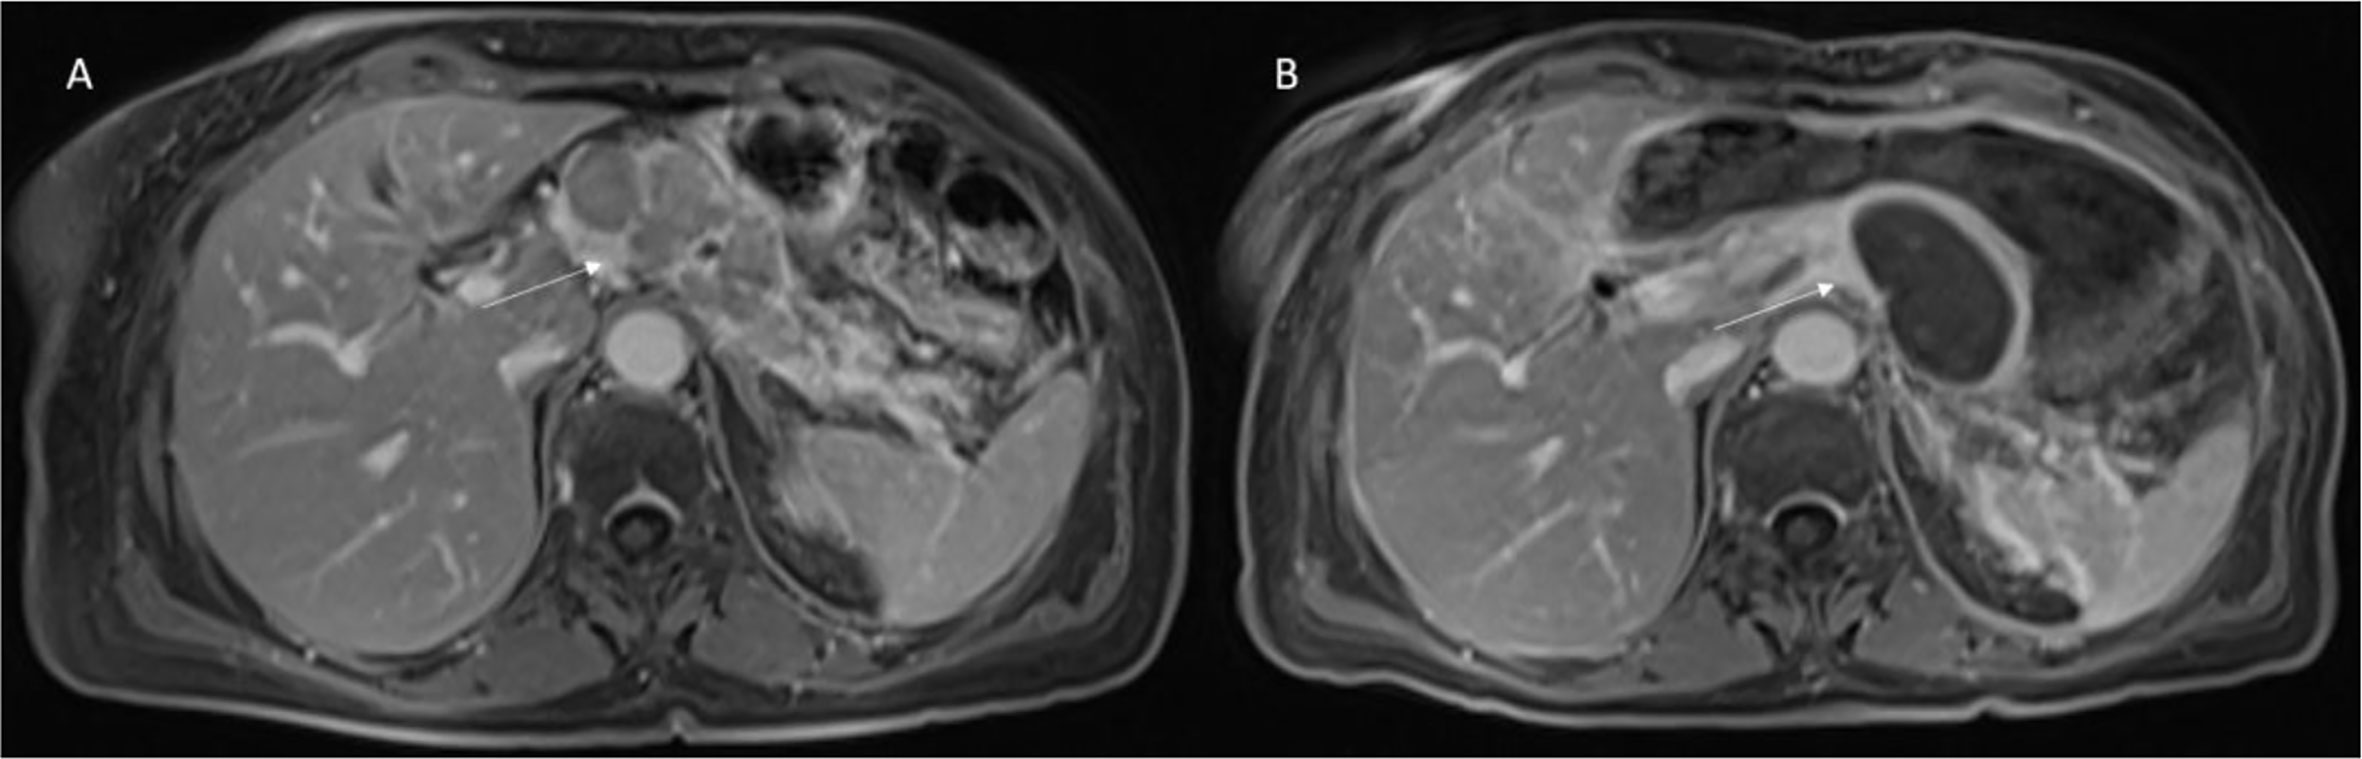

RFA causes heterogeneous appearances on imaging in the ablated areas, correlated to the therapy effects, such as interstitial edema, hemorrhage, carbonization, necrosis, and fibrosis (Figure 2).

Figure 2 Patient 1 with Body-Tail Pancreatic Cancer. Morphological MRI assessment post-RFA treatment. In (A) (VIBE T1-W post-contrast sequence during portal phase in axial plane) pre-treatment evaluation of lesion (arrow). In (B) (VIBE T1-W post-contrast sequence during portal phase in axial plane) arrow shows ablated area. Qualitative assessment shows significant differences in SI in pre- and post-treatment sequences.